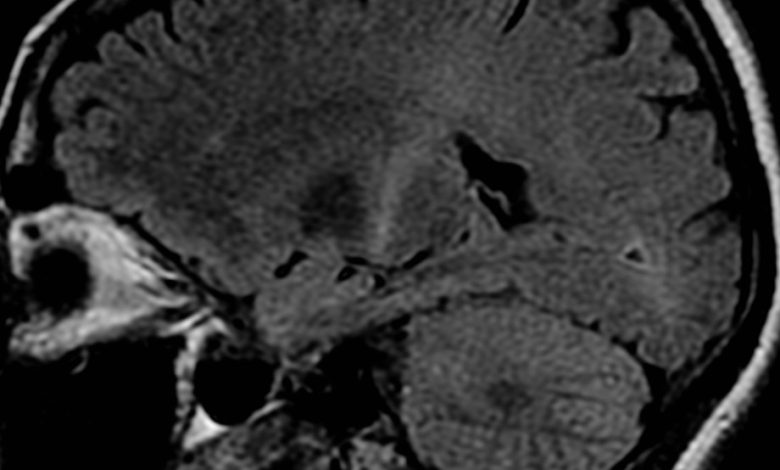

Uma ressonância magnética com aumento de sinal na parte posterior da cápsula interna que pode ser rastreada no córtex motor consistente com o diagnóstico de ELA. Crédito: Frank Gaillard/Wikipedia